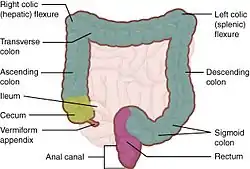

| Colic flexures | |

The hepatic and splenic flexures labelled at either side of transverse colon | |

In the anatomy of the human digestive tract, there are two colic flexures, or curvatures in the transverse colon. The right colic flexure is also known as the hepatic flexure, and the left colic flexure is also known as the splenic flexure.[1] Note that "right" refers to the patient's anatomical right, which may be depicted on the left of a diagram.

Right colic flexure

The right colic flexure or hepatic flexure (as it is next to the liver) is the sharp bend between the ascending colon and the transverse colon. The hepatic flexure lies in the right upper quadrant of the human abdomen. It receives blood supply from the superior mesenteric artery.

Left colic flexure

The left colic flexure or splenic flexure (as it is close to the spleen) is the sharp bend between the transverse colon and the descending colon. The splenic flexure receives dual blood supply from the terminal branches of the superior mesenteric artery and the inferior mesenteric artery.[2]